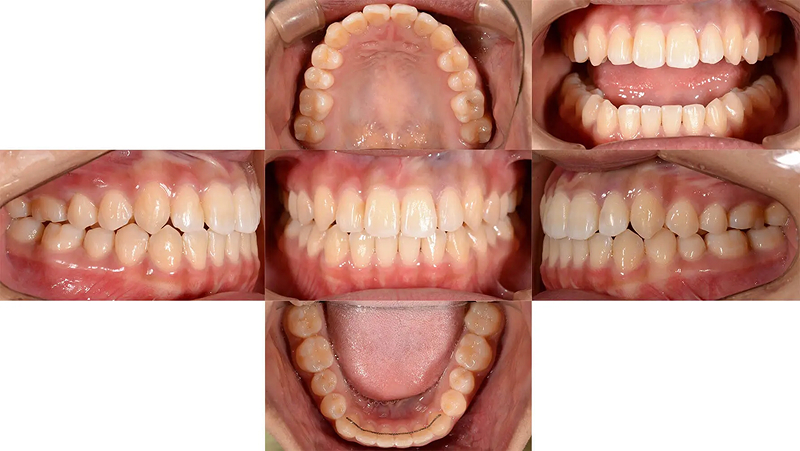

Case02マウスピース型矯正で前歯の凸凹を改善した部分矯正

前歯の凸凹が気になると受診されました。ただ、従来の矯正装置は付けたくないとのことで審美矯正を希望されました。本来なら全顎矯正の適応ですが、費用の兼ね合いもあり、前歯の凸凹だけ治療しても、審美的な改善はもちろん、機能的にも問題ないと診断しました。14枚(上下で28枚)以内のインビザライン ライトを適応しました。短期間できれいになったと大変満足していただけました。

口元比較

Before

After

初診 2016.5.16

矯正治療開始 2016.6.29

ファイナル 2017.1.4

| 主訴 | 前歯の凸凹を目立たない矯正で治したい |

|---|---|

| 診断 | 右側アングル1級、左側アングル3級の叢生 |

| 矯正方法 | マウスピース型矯正(インビザライン ライト) |

| 矯正期間 | 6か月・8回 |

| 費用 | 390,000円(税別) |

| 調整料 | 月1回 5,000円(税別) |